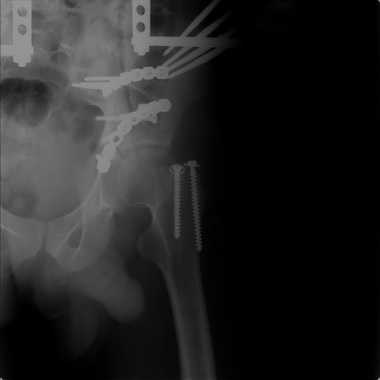

Добрый вечер уважаемые коллеги. Прошу прощение за долгое молчание( компьютер был в

долгосрочном ремонте). Больного с 9-ти месячной травмой таза мы прооперировали.

Оценив свои возможности и совместив с вашими рекомендациями и советами( большое спасибо

Рункову!), пошли задне-наружным доступом, с отсечением большого вертела. Закрепились

2-мя пластинками. Сверху закрепили аппаратом( передней рамой). На область перелома самого

гребня повздошной кости не вмешивались. Снимки высылаю. Жду ваших отзывов и комментариев.

Всем большое спасибо за активное участие в лечении больного. С ув.Андрей